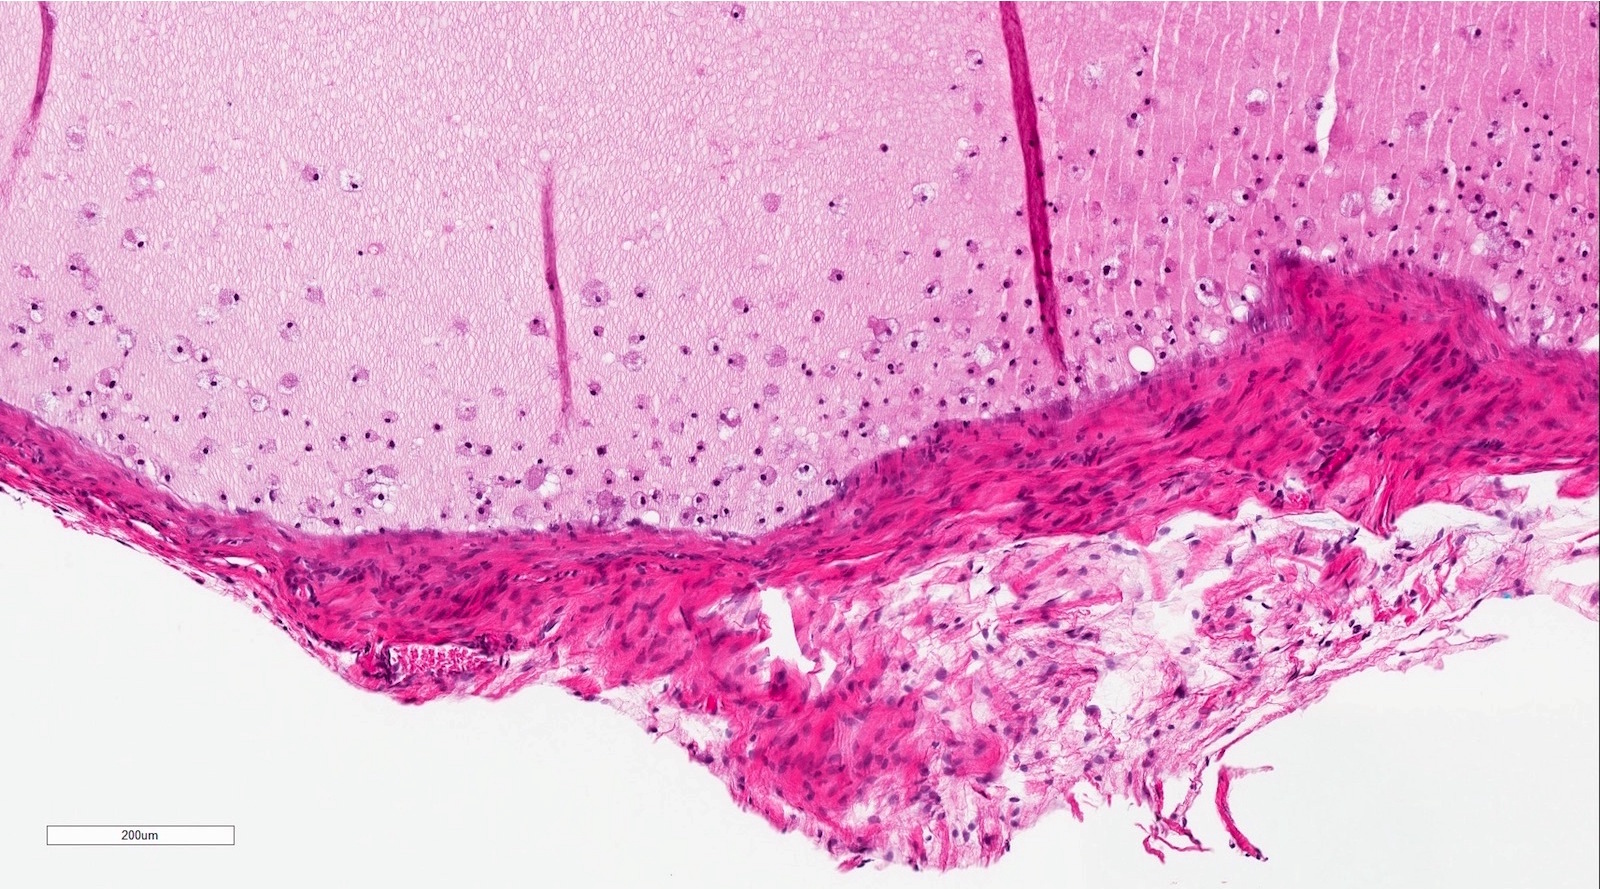

Microscopic (histologic) description

- If removed intact

- Pseudocyst cavity containing mucin, abundant epithelioid foamy histiocytes (muciphages), neutrophils and granulation tissue (Acta Histochem 2014;116:40)

- Long standing lesions organize into fibrosis resembling a fibroepithelial polyp (Acta Histochem 2014;116:40)

- No epithelial cyst lining, may see overlying surface oral mucosa with variable atrophy in superficial mucoceles (J Oral Maxillofac Surg 2011;69:1086)

Microscopic (histologic) images